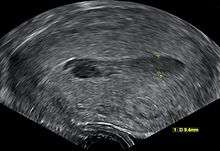

Although hematometra can often be diagnosed based purely on the patient's history of amenorrhea and cyclic abdominal pain, as well as a palpable pelvic mass on examination, the diagnosis can be confirmed by ultrasound, which will show blood pooled in the uterus and an enlargement of the uterine cavity.[4][5] A pyelogram or laparoscopy may assist in diagnosing any congenital disorder that is suspected to be the underlying cause of the hematometra.[2]